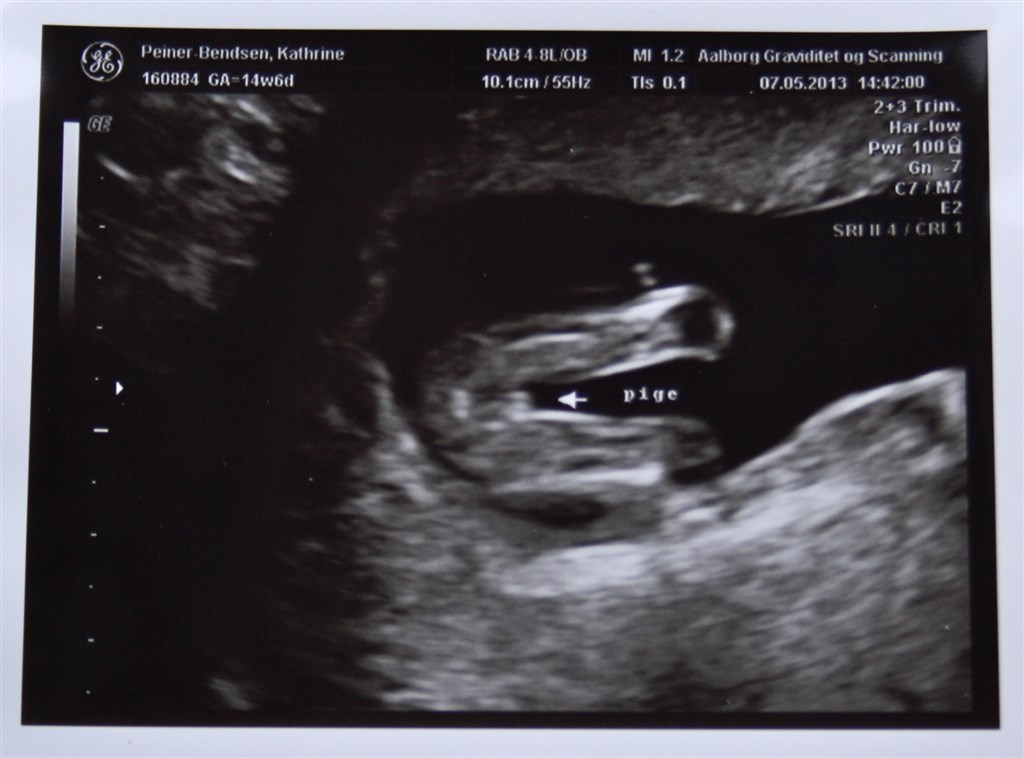

I følge kønsscanningen venter vi en lille pige, men da vi ikke fik noget bekræftet ved md-scanningen kan jeg alligevel ikke lade være med at tvivle lidt

Så hvad siger i? Dreng eller pige?

Vedhæftede fotos (klik for at se i fuld størrelse)